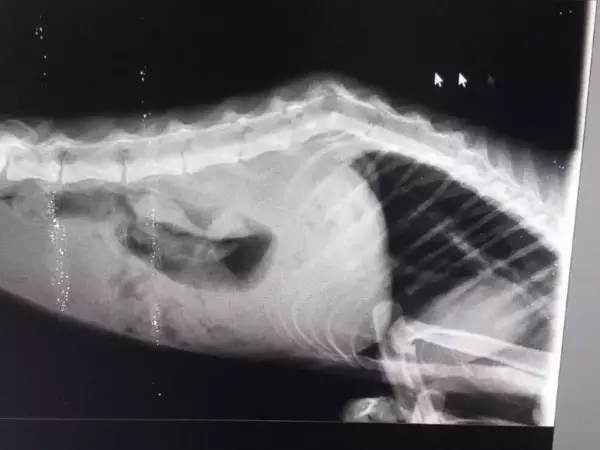

Кошку со следами от зубов собаки на спине нашли в хуторе Красновка. Неравнодушные прохожие решили отвезти травмированное животное в ветеринарную клинику. Там врачи выяснили, что у пациентки сломан позвоночник. Даже после нескольких процедур ходить Венера больше не смогла.